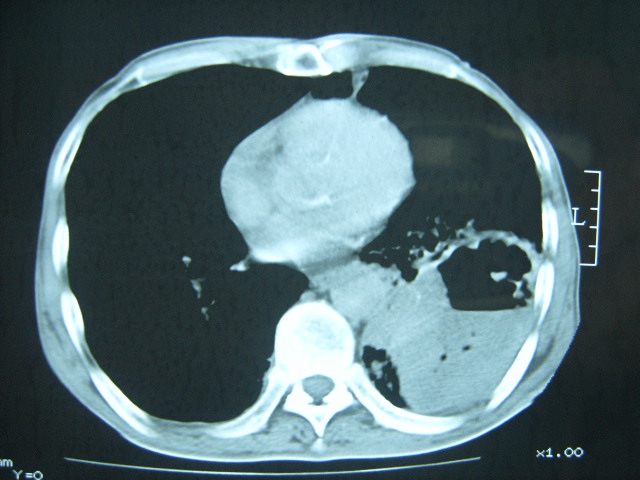

男74岁,咳嗽,寒战,低烧。有糖尿病史。

糖尿病并发肺脓肿建议治疗后复查

两肺慢性炎症伴脓肿形成,不除外继发霉菌感染。

1、左下肺肺脓肿,合并霉菌球形成?.2、双肺陈旧性病灶.3、右上肺病灶警惕瘢痕癌,建议定期复查.

两肺结核,左下肺大片实变,内见空洞性病变,壁不规则,结合糖尿病史,考虑:结核性?霉菌性?建议结合实验室检查或治疗后复查。